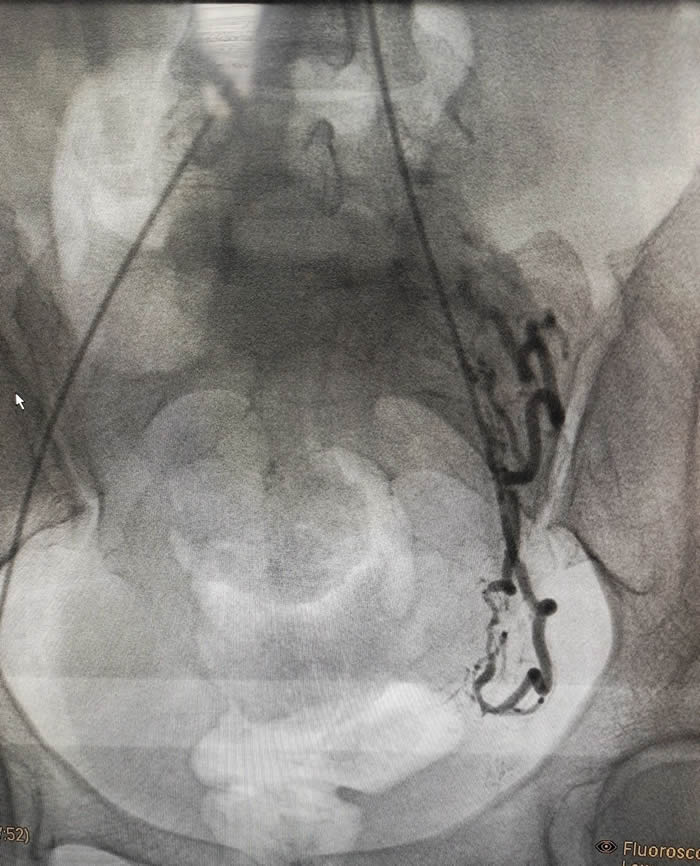

麵對如(rú)此危(wēi)急的病情(qíng),徐州市婦幼保健院迅速啟動多學科協作機製。婦科、產科、介入科、麻醉科、輸血科等多科室專家團隊緊(jǐn)密配合,共同為(wéi)孕婦生命安全保駕護航。最終(zhōng)通過通力協作(zuò)、默契配合,通過血管栓塞介入治療、藥物引(yǐn)產和刮宮手術(shù),最終轉危為安。

術中(zhōng)介(jiè)入(rù)科楊剛、杜長江主任(rèn)團隊率(lǜ)先行動,通過子宮動脈栓塞(sāi)術(UAE)阻斷供應(yīng)胎盤的主要血管,有效減少了術中出血的(de)風險。這種微創技術不僅創傷小,還能為後續引產和(hé)刮宮手(shǒu)術提(tí)供安全保障(zhàng)。

隨後,婦科梁(liáng)麗主任團隊在藥物(wù)引產的基礎上,通過手術清除殘(cán)留妊娠組織。整個過程中,麻醉科(kē)團隊全程監控孕婦(fù)生命體(tǐ)征,確保手術順利進行。輸血科則為(wéi)可能出(chū)現的(de)大出血隨時準備提供(gòng)血液支持。

這場成功的救治不僅體現了徐州市婦幼保健院在高(gāo)危妊娠管理方麵的高水平,也(yě)彰顯了多學科協(xié)作的強大優勢。子宮動脈(mò)栓塞術作為一種先進的介入治療技術(shù),已被廣泛應用於前置胎盤和胎盤植入治療(liáo)中。它不僅能有效減少術中出血(xuè),還能最大限(xiàn)度地保留產婦的生(shēng)育功能。此外,藥物引產和刮宮手術的結合也為高危妊娠處理提供了新(xīn)的思(sī)路。這(zhè)種綜(zōng)合治療方案在降低手術風險(xiǎn)的同(tóng)時,減(jiǎn)小(xiǎo)了患者痛苦。